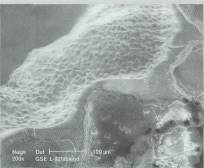

damarlarının organik bir iskeleti oluşturuluyor. Bu iskeleti oluşturduktan sonraki aşamaysa hücrelerin oluşturulması. Damar iskeleti çevresine yerleştirilen karaciğer hücreleri, belirli büyüme faktörleri yardımıyla çoğalarak organın kalın etli kısmını oluşturuyorlar. Bir sonraki aşamaysa damarın oluşturulması. Bunun için süngerimsi yapıda olan PLGA içine damar hücreleri enjekte ediliyor. İskelet, hücrelerin çoğalması için gerekli büyüme faktörlerini ve besin maddelerini içeriyor. Damar hücreleri iskelet boyunca ilerleyerek karaciğer hücrelerine yapışıyor. Burada çoğalan damar hücreleri, iskelet çevresinde birleşerek tam bir damar yapısı oluşturuyorlar. PLGA iskelet birkaç ay içinde kendiliğinden eriyerek geride karaciğer hücreleri ve içinde damarları olan yapay bir organ bırakıyor. Bu şekilde oluşturulan yapay karaciğer hayvanlarda denendi. Oldukça iyi kan akımının sağlandığı bu organlarda dışarı kan sızıntısı da gözlenmedi.

Yapay karaciğer oluşturmak, teknik açıdan oldukça güç. Poliüretan köpük iskelet kullanan bilim adamları yapay karaciğer oluşturabiliyorlar. Köpük içine yerleştirilen karaciğer hücreleri, mikrokümeler oluşturuyor. Elde edilen üç boyutlu yapay karaciğer vücut dışında 10 gün süreyle işlev görüyor. Karaciğer yetmezliği olan domuz ve farelere yerleştirilen bu yapay karaciğerler oldukça iyi sonuçlar verdi. Bilim adamları, deney aşamasındaki köpük karaciğerleri daha da geliştirerek, insanlarda kullanımı için çalışıyorlar.